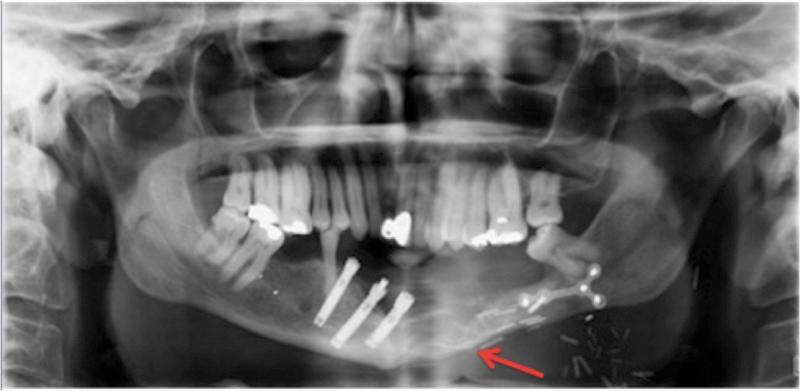

Ameloblastoma is a locally aggressive tumor that most commonly arises in the mandible. It has a high rate of recurrence if inadequately excised. We report a case of a patient who developed recurrence of his ameloblastoma in his fibula flap mandibular reconstruction despite clear resection margins 23 years after resection. This is the first reported case of recurrent ameloblastoma in a neo-mandible reconstruction in the setting of negative margins. We discuss its surgical management using digital planning and reconstruction using a contralateral free fibula flap. Ameloblastoma is a locally aggressive entity that requires complete excision. Recurrence can even occur in the reconstruction, which can present a challenge to manage. Consideration should be given to repeat excision and second osseous flap reconstruction.

成釉细胞瘤是一种具有局部侵袭性的肿瘤,最常发生于下颌骨。如果切除不充分,其复发率很高。我们报告一例患者,在切除23年后,其腓骨瓣下颌骨重建中的成釉细胞瘤出现复发,尽管切除边缘清晰。这是首例在切缘阴性情况下新下颌骨重建中复发性成釉细胞瘤的报道病例。我们讨论了使用数字规划进行手术管理以及使用对侧游离腓骨瓣进行重建的情况。成釉细胞瘤是一种需要完整切除的局部侵袭性病变。复发甚至可能发生在重建过程中,这给治疗带来了挑战。应考虑再次切除和二期骨瓣重建。